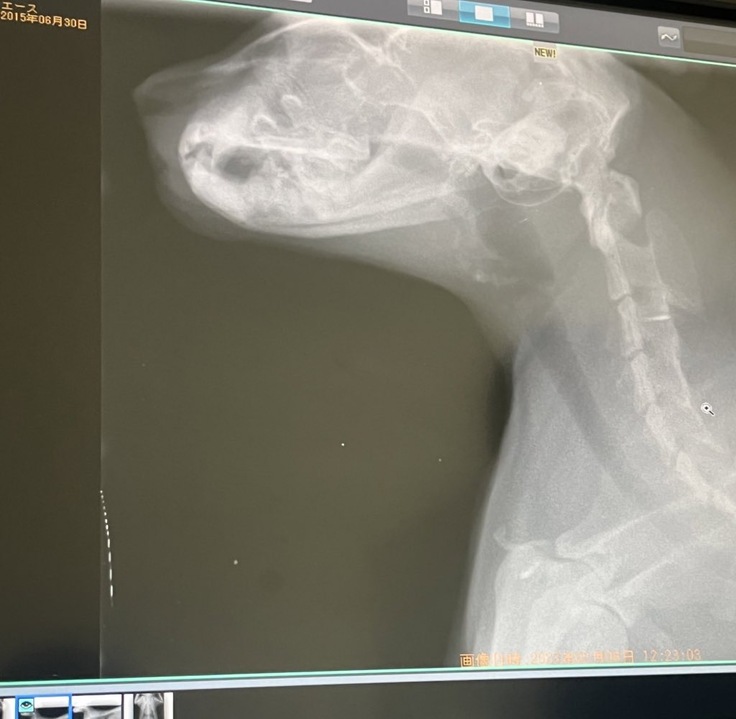

そちらで、レントゲンを撮り、ネブライザーとインターフェロンを打ちました。

そこでレントゲンの結果、鼻のところに白いモヤッとしてるような気がすると言われ、レントゲンでは詳しくわからないので、詳しく知りたいならCTと内視鏡をした方がいいと言われました。

そのときにもしかしたら腫瘍かポリープか何かあるかもしれないと言われ、一気に怖くなり、CTと内視鏡ができる病院をすぐに探し始めました。